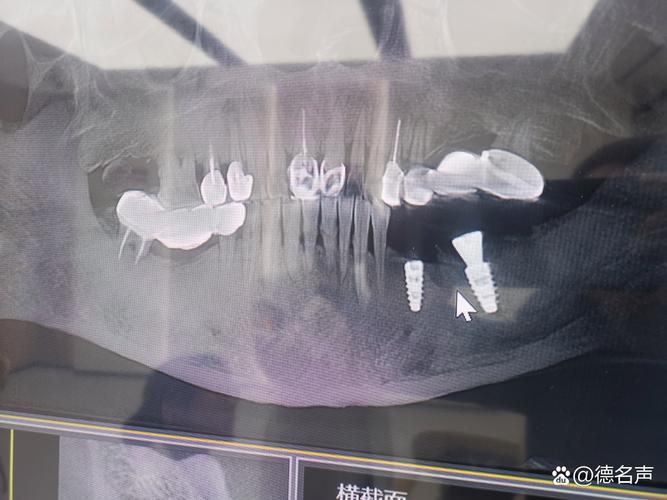

- 种植牙数量和位置: 单个种植牙的影响通常有限,多个种植牙或种植牙位于扫描野中心时,伪影范围会更大。